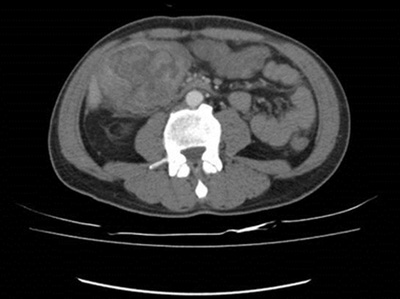

臺北市立聯合醫院仁愛院區血液腫瘤科林哲斌醫師解釋,假設將大腸由脾臟彎處區分成左、右大腸,升結腸屬右大腸,其中的糞便尚未成型,所以在此處形成的大腸腫瘤不易早期發現,較常像林先生的狀況,等到貧血了才被發現,腫瘤也長大到7.4公分。